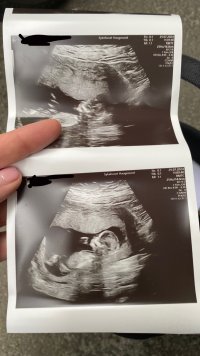

Var på TUL i dag 13+3. Hun mente det kunne se ut som jente men ville ikke bekrefte noe. Hva tror dere? :)

Jeg har ikke peiling på sånt! Men jeg synes det ser ut som en gutt, eller.. jeg vet ikke:smiley-ashamed004

Du kan evt spør i en gruppe på fb :Heartred